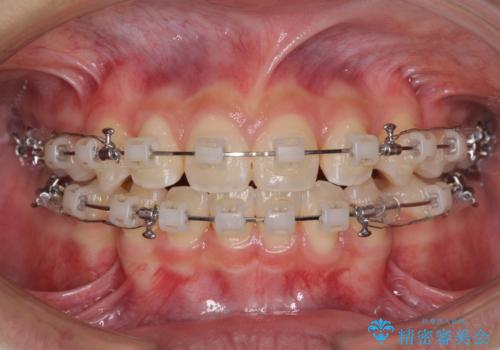

- クリアブラケット

- 2年4ヶ月

当初は八重歯やデコボコが一番気になっていましたが、抜歯矯正により口元の突出感が改善されるにつれ、口の閉じやすさを実感するようになってきました。

部活動で調整来院に来られないことがしばしばあり、期間は予定よりもかかりましたが、きれいに仕上げることができました。